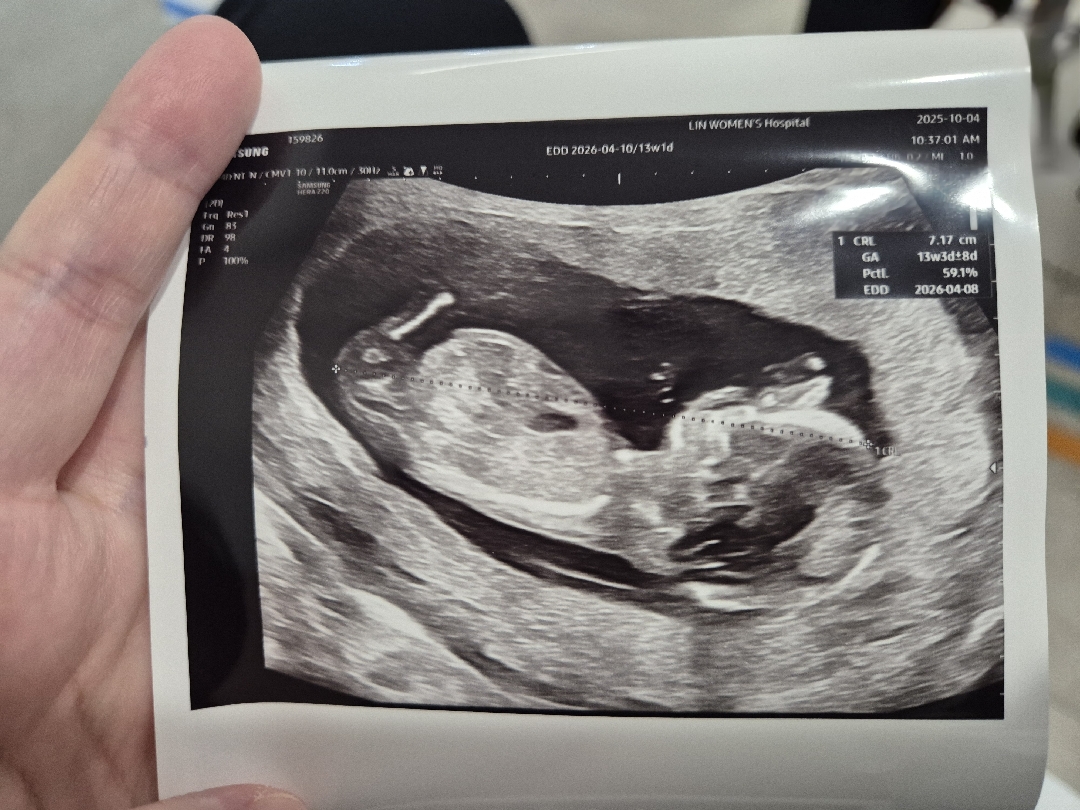

13주 초음파 사진 각도법 부탁드립니다!

초산이라 잘 몰라서 질문드려요 🥲